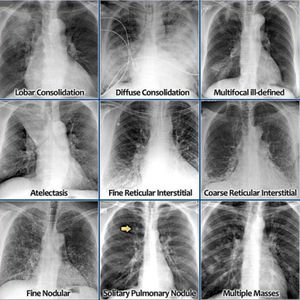

Chest X-Rays